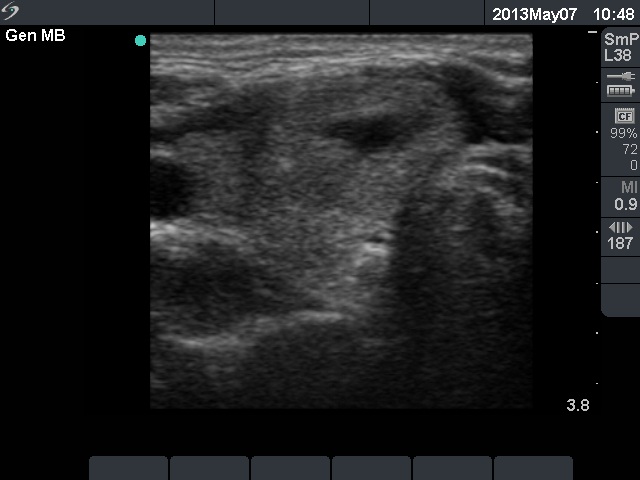

Right lobe, longitudinal scan

Right lobe, horizontal scan. There is a minimally hypoechogenic nodule presenting cystic degeneration in the ventromedial part of the lobe.